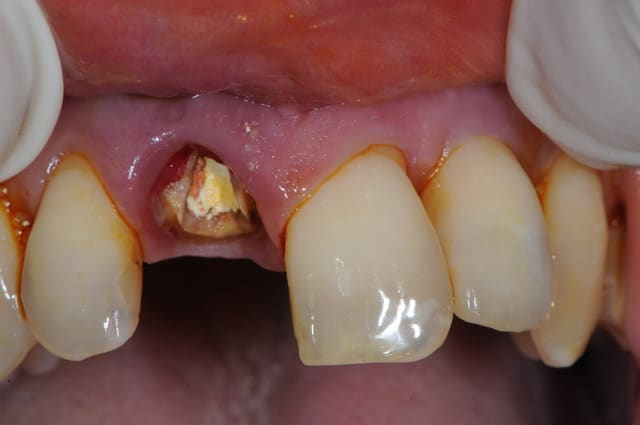

Vous tenteriez l'EII dans ce cas ci

Il y a 3.6 mm d'os au dessus du granulome

si tu veux aller au casse pipe....

pas que pour le granulome...d'ailleurs...mais aussi parce que tu as une belle fracture vestibulaire qui fait que la corticale...bein y en a plus...ou quasi plus...